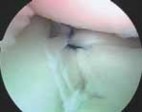

The surgical approach begins with the establishment of a standard posterior viewing portal, placed approximately 2 cm inferior and 1 cm medial to the posterolateral corner of the acromion. Upon entering the joint, a meticulous diagnostic sweep is performed. The surgeon must systematically evaluate the biceps anchor, the superior labrum, the articular surfaces of the humerus and glenoid, the rotator cuff footprint, and the entire capsulolabral complex. Particular attention is directed to the anteroinferior quadrant to confirm the presence of a Bankart or ALPSA lesion. The size and depth of any Hill-Sachs lesion are evaluated dynamically by taking the arm through a range of motion to assess for "engagement" over the anterior glenoid track.

The foundation of a successful arthroscopic stabilization is the meticulous mobilization of the capsulolabral complex. In chronic cases, the torn labrum and IGHL frequently heal in a medially displaced position along the anterior glenoid neck (the ALPSA lesion). Using a combination of arthroscopic elevators, rasps, and electrocautery, the surgeon must aggressively liberate this tissue from the scapular neck. The release must extend inferiorly to the 6 o'clock position to adequately mobilize the inferior capsule. Once the tissue is freed and can be easily reduced to the articular margin, the anterior glenoid neck is lightly decorticated using a motorized burr or rasp. This critical step removes fibrous tissue and exposes bleeding cancellous bone, creating an optimal biological environment for robust soft-tissue healing.